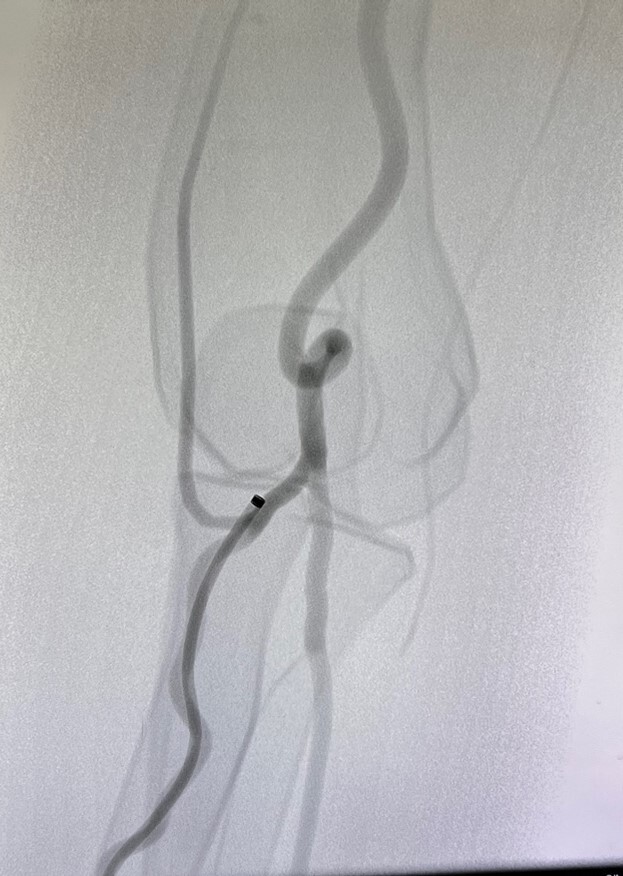

Abb. 5 Komplexe radiale Anatomie

Abb. 5: Komplexe radiale Anatomie (Mentice Vist)